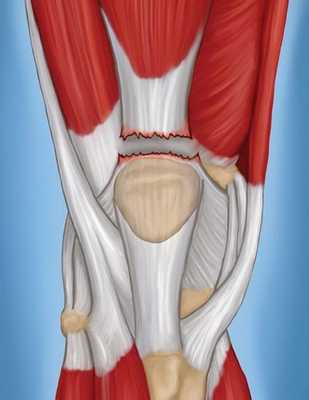

• Частичный или полный разрыв дистальных сухожильно-мышечных единиц группы четырехглавой мышцы бедра

о Нарушение целостности части сухожилия четырехглавой мышцы

- Разрывы сухожилий почти всегда возникают в области прикрепления надколенника или проксимальнее

о Разрыв начинается центрально и продолжается на периферию

• Полный разрыв сухожилия:

о Очаговое нарушение одного и более сухожильных единиц четырехглавой мышцы

о Вклиненная гематома при остром разрыве

о ± гемартроз/выпот, особенно при поражении промежуточной широкой мышцы

о ± отек внутри мышцы

о Низколежащий надколенник при крупном разрыве

о Укорочение сухожилия надколенника

о ± отек костного мозга кверху от надколенника

о Эти признаки лучше определяются на Т2 ВИ в режиме подавления сигнала от жира

• III степень = полный разрыв: очаговый полный разрыв одной или более сухожильных единиц

Полные разрывы. Характеризуются полным разделением сухожилия на два отдельных фрагмента. Важно отметить, что в этом случае пациент полностью утрачивает возможность совершать разгибательные движения в колене.

На изображении показано полное разделение сухожилия.